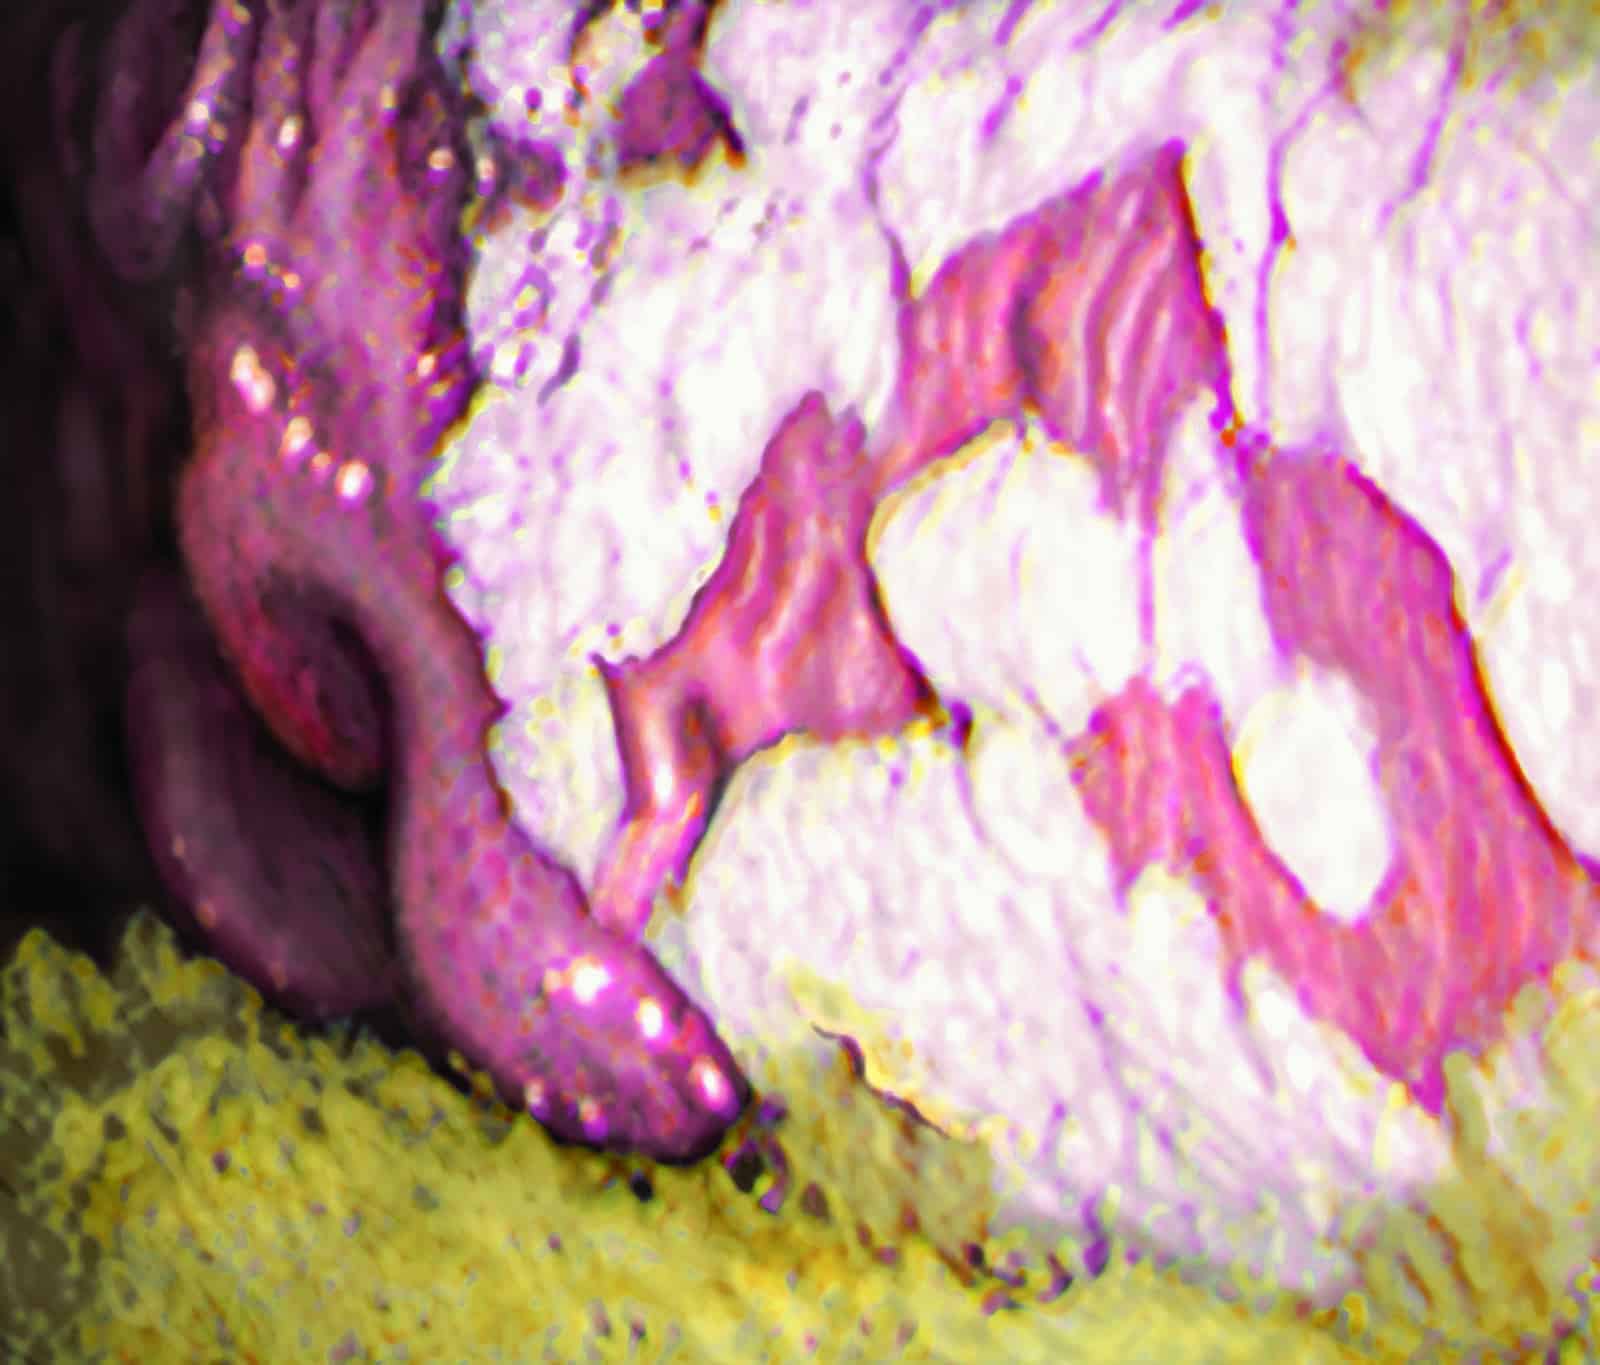

Mean glandular severity scores were significantly lower in the treatment group on Days 28 (shown) and 35, as seen on gastroscopy exam. | Courtesy Dr. Frank Andrews

Andrews and his team saw a significant weight increase in all horses, but the treatment did not affect body weight. The mean nonglandular EGUS and severity scores were significantly lower in the treatment group on Days 28 and 35.

“The nonglandular ulcers were healed, except for mild hyperkeratosis (callousing), on these dates as well,” Andrews said. “The mean glandular (ulcer) and severity scores were significantly lower after 14 days in the treatment group. The ulcers did heal, but some reoccurred in both groups of horses by Day 28, which is not uncommon in these types of ulcers.” The mean gastric fluid pH remained low and variable throughout the study in both groups. Many drugs when used long term block gastric acid, which can change the stomach’s physiology. In other words, this supplement contributed to gastric health without changing stomach acidity.